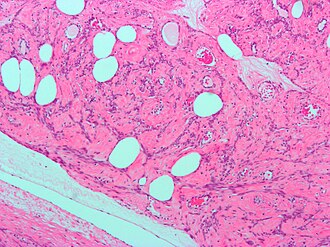

Template:Px Lipoleiomyoma. H&E stain. | |

- Lipoleiomyoma - with adipose tissue.

- Lipoleiomyoma1.jpg

Lipoleiomyoma - low mag. (WC/Nephron)